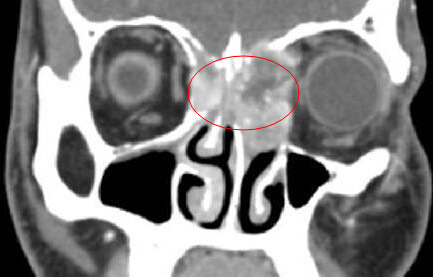

做的什么检查?鼻窦炎是需要做CT明确的,以及内窥镜这两个检查有做吗?

CT

CT还在吗?你微信多少,我加你,你稍后把CT片子发给我看一下